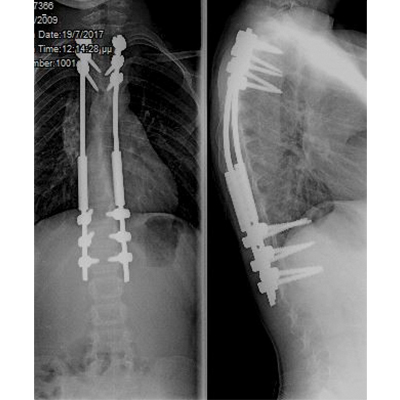

Σύνθετες παραμορφώσεις της σπονδυλικής στήλης όπως είναι η σκολίωση και η κύφωση, ακόμα και σε περιπτώσεις παιδιών με συγγενείς ανωμαλίες ή νευρομυϊκές παθήσεις, αντιμετωπίζονται χειρουργικά και στις μικρότερες ηλικίες. Τα σύγχρονα συστήματα σπονδυλοδεσίας επιτρέπουν τη διόρθωση της παραμόρφωσης, με παράλληλη επιμήκυνση της σπονδυλικής στήλης, ενώ το παιδί συνεχίζει να αναπτύσσεται και να ψηλώνει. Αποτέλεσμα είναι τα παιδιά - αλλά και οι οικογένειές τους - να ξεπερνούν με ασφάλεια και να αφήνουν οριστικά πίσω τους ένα δύσκολο πρόβλημα, όπως είναι μια παραμόρφωση της σπονδυλικής στήλης, συνεχίζοντας πια να αναπτύσσονται φυσιολογικά συμμετέχοντας σε όλες τις δραστηριότητες των παιδιών της ηλικίας τους.

Διατεινόμενη σπονδυλοδεσία σε παιδική νευρομυϊκή σκολίωση. Το παιδί συνεχίζει να ψηλώνει, καθώς η σπονδυλική του στήλη επιμηκύνεται.